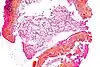

| Hematoxilina | Básica / Acidofílica | Tiñe núcleos, ácidos nucleicos y estructuras basofílicas (mitocondrias y ribosomas) en azul. | Tinción histológica general | ![]() |

| Eosina | Ácida / Basofílica | Tiñe proteínas y estructuras con afinidad por los ácidos en diferentes tonos de rojo | Tinción histológica general | ![]() |

| Tinción hematoxilina-eosina | Bicomponente Anfifílica |

|

Tinción histológica general | ![]() |